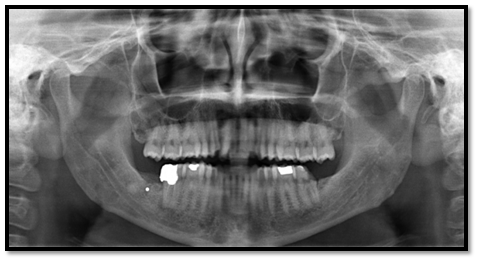

A 35-year-old male patient reported to college of Dentistry, Jazan. In routine examination of the other teeth on OPG (Orthopantamogram), it was found that a sharply defined radiopaque mass in the right mandibular third molar area (Figure 1). On history, patient had undergone surgical extraction of the third molar at a private clinic one year back. There was no history of pain, swelling, discharge or paresthesia in that region. Based on history, clinical and radiological correlation, the object was assumed to be a broken fragment of bur. The broken bur fragment was buried in the region approximately 5 to 7mm from the upper border of alveolus and 7 to 8mm away from the distal root of right mandibular second molar. As patient was not having any of the signs and symptoms related to that broken bur fragment, no treatment was done and patient was kept on constant observation.

Figure 1 OPG showing the buried broken fragment of round bur in the right mandibular third molar area.